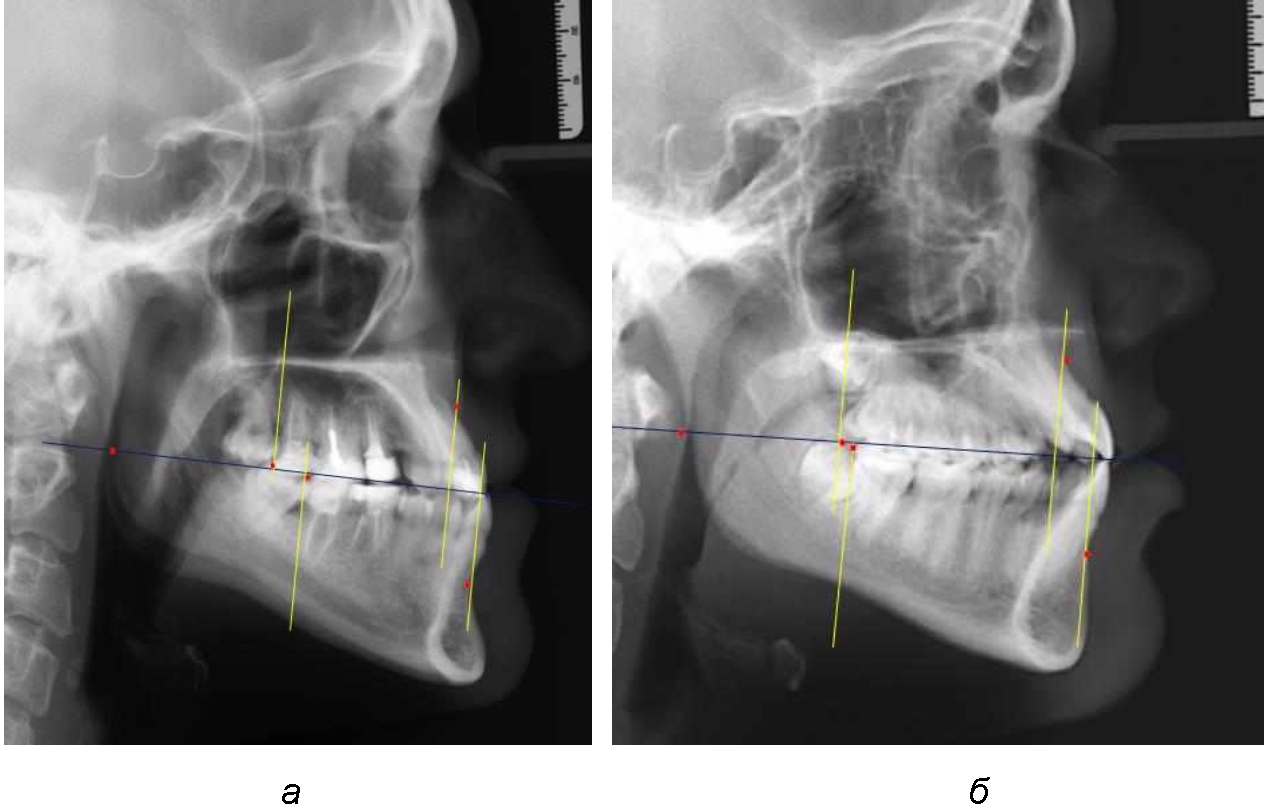

При сагиттальной патологии прикуса встречались варианты, при которых отмечалось равенство либо не равенство альвеолярно-ден-тальных размеров челюстей. Однако вне зависимости от этого, как правило, была отмечена разница в положении челюстей, измеряемая от конструируемой точки «rmРOcP» до точек апикальных базисов по Downs. С дистальной окклюзией было 20 снимков и с мезиальной окклюзией – 19 снимков.

Характерной особенностью мезиальной окклюзии было увеличение расстояния между проекционными апикальными точками, при котором существенно смещалась кпереди нижняя челюсть, а Wits-число имело отрицательные значения. Также дистальная точка нижнего моляра была расположена кпереди от верхней дистальной точки окклюзии второго моляра. Относительно равными считались показатели альвеолярно-дентальных размеров, при которых разница не превышала 1,5 мм. Тем не менее расстояние «rmРOcP-B(SM)» превышало расстояние «rmРOcP-A(SS)» в среднем по группе на (6,87 ± 1,62) мм, что свидетельствовало об аномалии положения челюстей, при котором визуально нижняя челюсть располагалась впереди верхней челюсти (рис. 3).

Рис. 3. Положение апикальных точек и челюстей при мезиальной окклюзии с равными (а) и разными (б) альвеолярно-дентальными размерами зубо-челюстных дуг

В тех случаях, когда при мезиальной окклюзии альвеолярно-дентальные размеры были различными, размер нижней челюсти превышал аналогичный параметр верхней челюсти в среднем на (3,74 ± 1,28) мм.